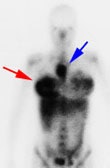

Hodgkins Lymphoma and Mastitis: The patient shown in the images below was a post-partum lactating female who presented for a baseline Ga-67 exam as part of her staging work-up for Hodgkins lymphoma (nodular sclerosing subtype). The planar whole body images demonstrate abnormal uptake of gallium within the patient's primary tumor in the mediastinum (blue arrow). Breast uptake is seen bilaterally (consistent with the patients history of lactation), but is asymmetric- right greater than left (red arrow). SPECT imaging was also performed (right). Asymmetric breast uptake was concerning for lymphomatous involvement of the breast, but on examination the patient was found to have a right breast mastitis. (Click images to enlarge) |